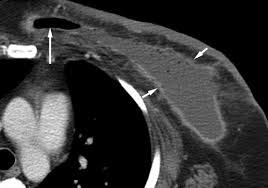

Bone scans, positron emission tomography (pet), and computed tomography (ct) all continue to be employed alone or in combination for the detection of breast cancers suspected to have spread. Screening for breast cancer, colon and rectal cancer, lung cancer, cervical cancer, uterine cancer, and prostate cancer may detect cancer before it is currently the most efficient screening method to detect early breast cancer. Pet/ct scan combinations detect cancer in its earliest stages, when changes are happening at the cellular level. It takes pictures from different angles. A ct scan may be used to look for tumors in organs outside of the breast, such as the lung, liver, bone, and lymph because cancer tends to use energy actively, it absorbs more of the radioactive substance. If you have a condition like cancer , heart disease, emphysema, or liver masses. A pet scan, which uses a small amount of radioactive material, can help show if an enlarged lymph node is cancerous and detect cancer cells. What cancers can be detected by ct scans? Mammogram and breast us may sometimes be better. Ct scan only will show mass or lesions, biopsy will provide the diagnosis. Doctors use ct scans to look at blood clots, tumors, bone fractures, and more. A scanner then detects this substance to produce. A chest computed tomography (ct) scan is an imaging test that takes detailed pictures of the lungs and the inside of the chest.

Learn more about how the test is done and what. Computed tomography (ct) scan is a useful diagnostic tool for detecting diseases and injuries. Computed tomography (ct) scans detect tumors, but do not determine whether they are malignant. Ct is not good for diagnosing the breast cancer although. Learn how this test works, as well as its benefits and risks. Ct scans can detect bone and joint problems, like complex bone fractures and tumors. This lung cancer awareness month learn how future processing is able to detect lung cancer from ct scans with the help of ai. Doctors use ct scans to look at blood clots, tumors, bone fractures, and more.

Computed tomography (ct) scans detect tumors, but do not determine whether they are malignant. Imaging currently has the greatest effect for: In some cases, physicians use all three imaging techniques. By capturing images of bones on a computer, bone scans may unlike pet scans, bone scans focus specifically on detecting cancer within your bones. This provides a series of images from many different angles. How do ct scans work? A chest computed tomography (ct) scan is an imaging test that takes detailed pictures of the lungs and the inside of the chest. Ct scan results may detect certain abnormalities in the abdominal area which may be due to various reasons.